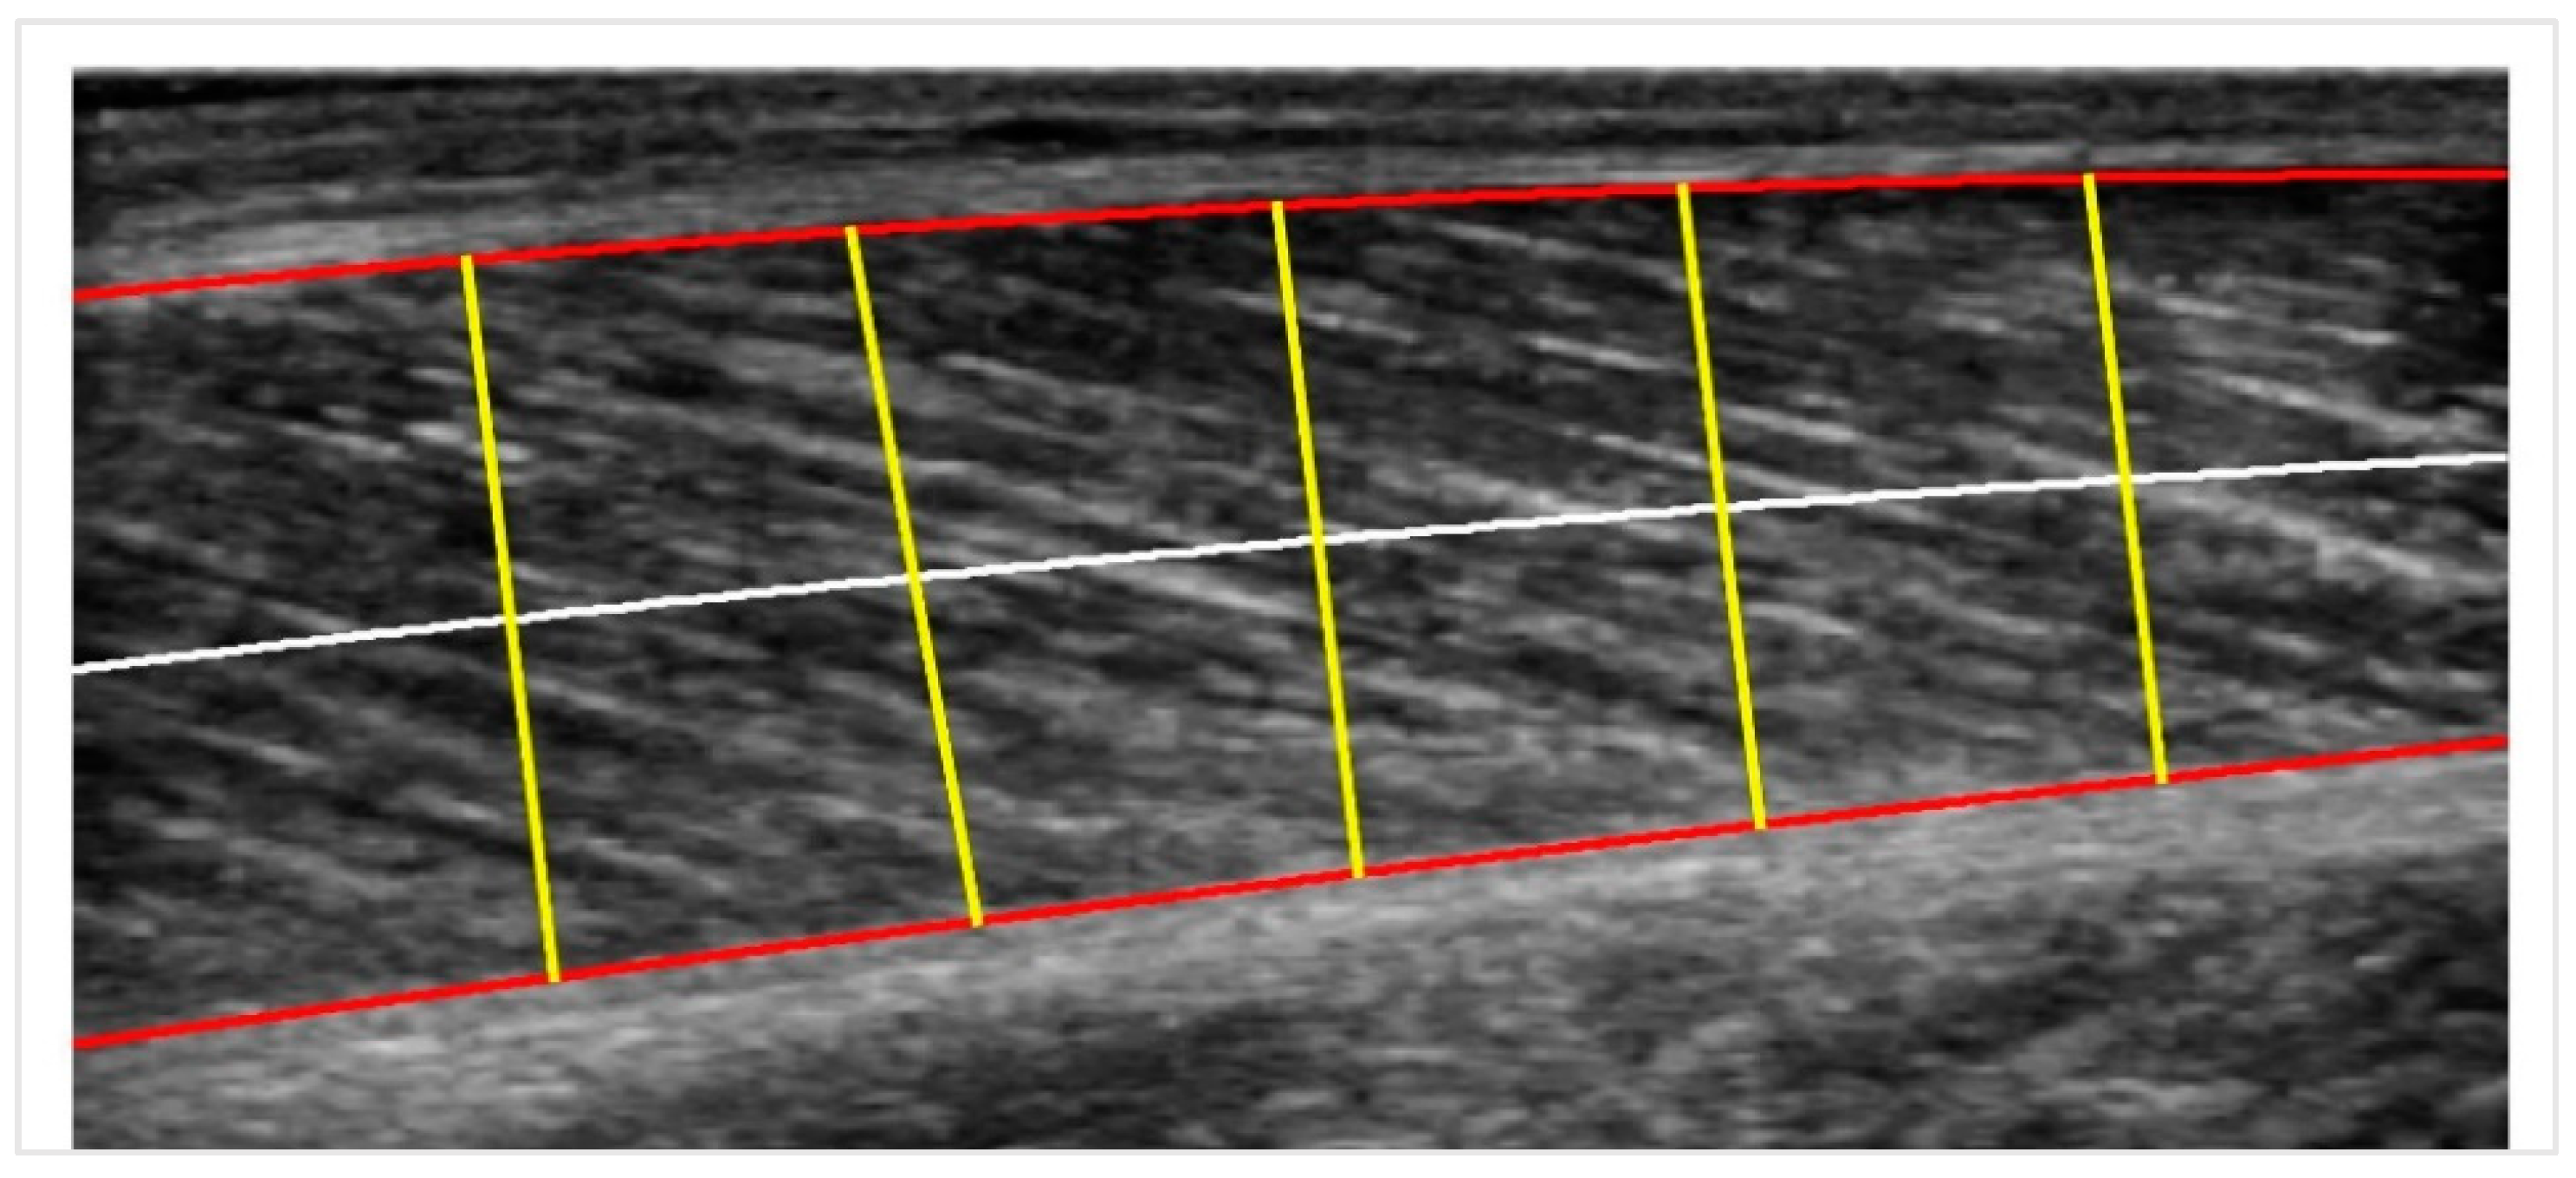

We follow some modifications and improvements to the basic pipeline procedure described in [18] (MUSA) to measure the muscle thickness. It is known that the muscle thickness in the longitudinal plane is defined as the distance between the superficial and deep aponeuroses. Still, due to its variability along the longitudinal axis, it can be better approximated by cutting the muscle into a few sectors, computing each sector’s distance and taking their mean value as output.

In particular, a centerline is drawn midway between the superficial and the deep aponeuroses. Then, for each point of the centerline, a chord perpendicular to it is plotted. The length of this chord is the measure of muscle thickness at that point. The average distance for all the chords along the centerline is the centerline distance. The number of sectors is chosen to be five, and the procedure is illustrated in Figure 4. In the last step, the pixels are transformed into physical units (mm) by multiplying by a scale factor retrieved from the DICOM metadata provided by the ultrasound machine.

Figure 4. Centerline Distance: the red curves are the two boundaries; the white line is the centerline, and the yellow lines are the perpendicular chords to the centerline used for calculating the muscle thickness.